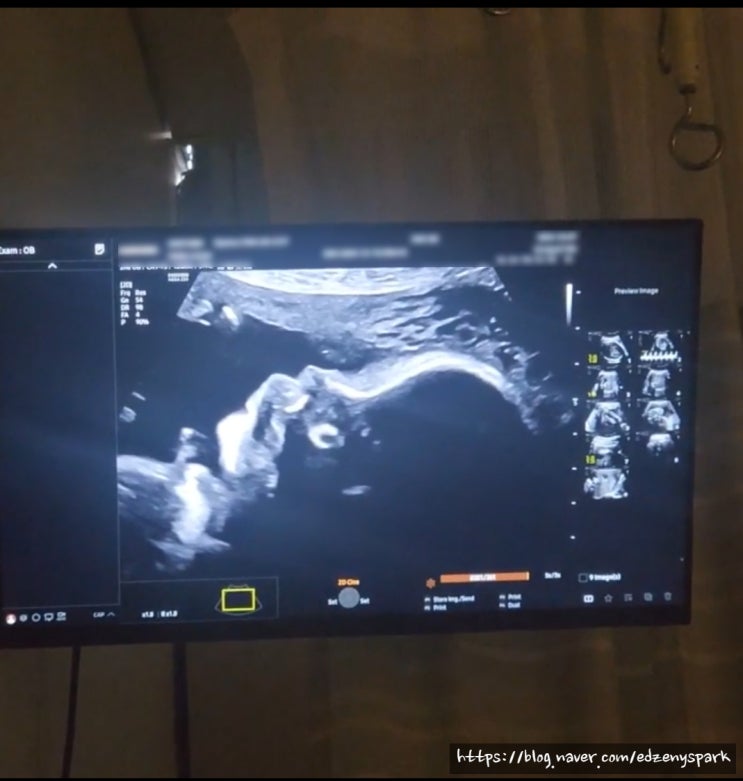

열달기록: 31주(결혼기념일 맞이 인스파이어/산전요가/후기임신증상)

31주 시작~! 어느덧 장화크기가 되버린 우리하트❤️ 크기가 커진만큼 태동이 엄청나다 스위티가 요새 잘때...